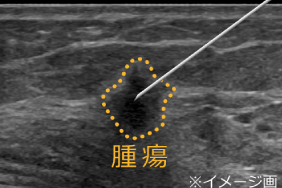

腫瘍を疑う病変が見つかった場合、細胞診断や組織診断を受けます。

採血を受けるときと同じくらいのサイズの注射針(当院では0.7mm)を腫瘍に刺し、細胞を吸引して採取し、ガラスに吹き付けたものを、病理医に診断してもらう方法です。 麻酔は使わず、傷跡も残りませんが、採取された細胞の量などから、確定診断できない場合があります。

〇組織診断

針生検という方法で、局所麻酔をしてから組織採取ができる専用の針(当院では太さ2.1mm)を使い、腫瘍の一部を小さなかたまりで採取し、これを病理医に診断してもらう方法です。